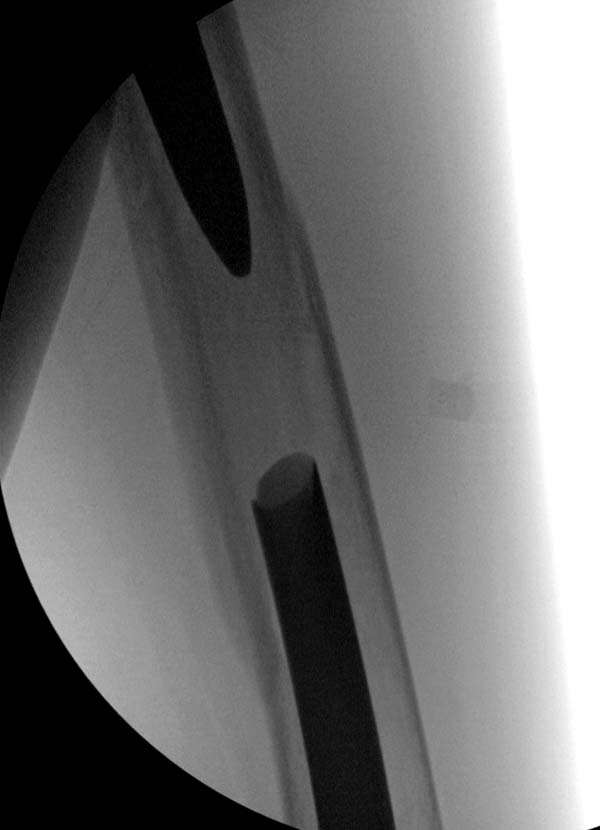

Наши операционные оснащены разными сверхскоростными алмазными и другими

режущими инструментами типа Midas Rex. Но моя двухдневная ручная работа

не дала результатов, и выемка для протеза получился неглубокой. Помогла

смекалка, за бутылку наш русский токарь исправил глубину за пять минут.

Гвоздь из ретроградного гвоздя DePuy в 15 мм получился немного тоньше,

чем у Российских коллег.

Операция не обошлась без казуса, при подготовке гвоздя произошла ошибка

в расчете. Пришлось коррегигировать по ходу операции, где длинный

дистальный отдел гвоздя срезали во время операции.